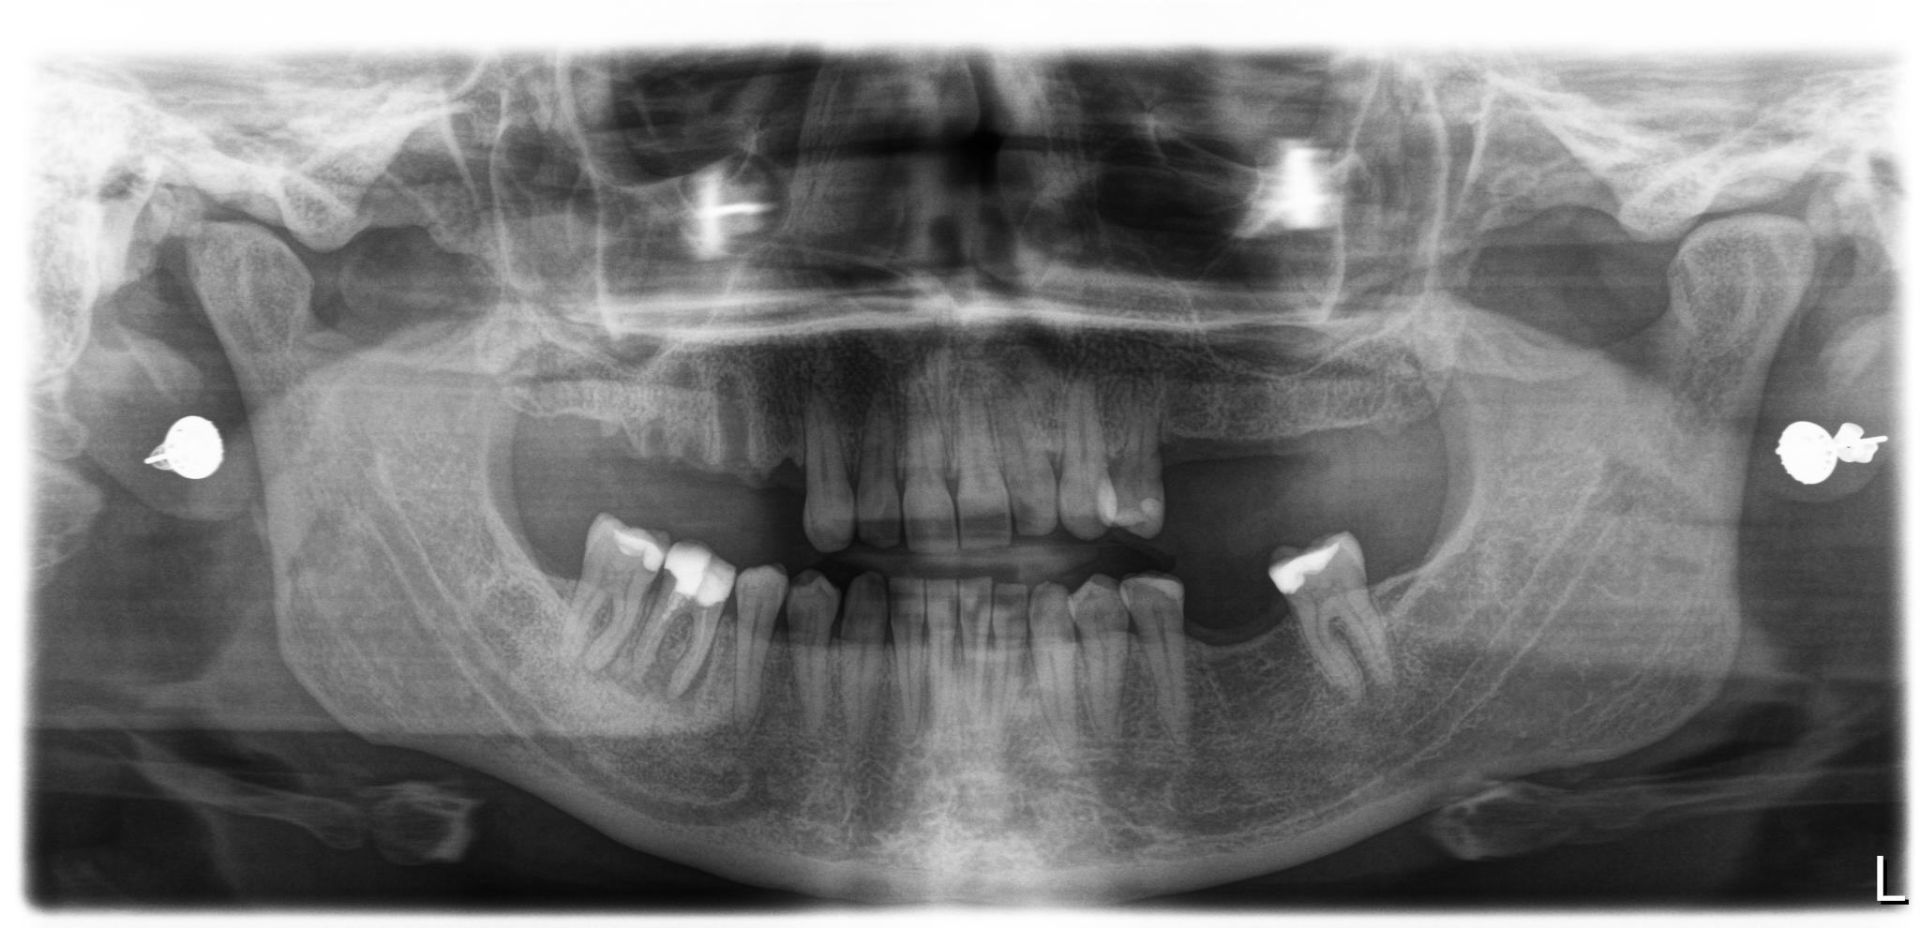

There is no question that dental implants have revolutionized tooth replacement and the practice of dentistry. Today’s highly successful dental implants consist of an artificial tooth root, to which a crown is attached. This system looks just like the natural teeth in your mouth when you smile: there is no visible difference. In addition, Implants do not decay and are relatively free from developing gum disease.

The practice of implant dentistry requires expertise in planning, surgical placement and crown fabrication: it is as much about art and experience as it is about science. It also requires teamwork between you and your dentist, and implant surgeon, and a dental technician.

Single Dental Implant